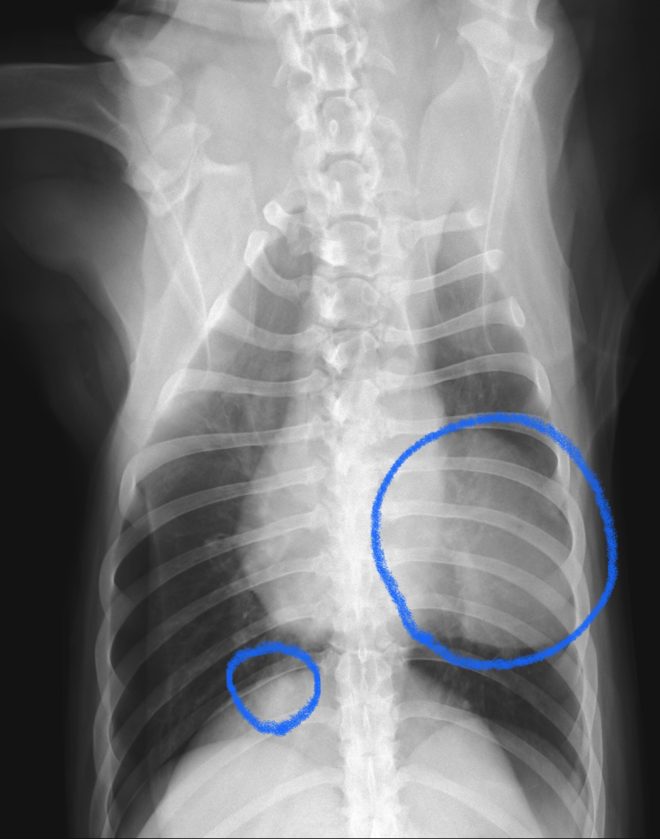

今回治療させていただいたワンちゃんは、これまで供血に協力してくれて、たくさんの命を繋いでくれたワンちゃんで、関節鏡検査の麻酔前検査で肺にしこりが見つかりました。肺には7cmほどのしこりがありましたが、本人に自覚症状はなく至って元気でした。

CT検査では、左前葉に7cmのしこりが1つ、右後葉に2cmのしこりが1つ見つかりました。お腹や、頭の方には腫瘍らしき病変はなく、転移性の肺腫瘍は否定的でした。左右の肺にしこりがあり、肺の中で転移している可能性が考えられましたが、その他には肺内転移を疑う病変がないため手術は可能と考えて、飼い主さんと相談の上、両方とも切除することになりました。